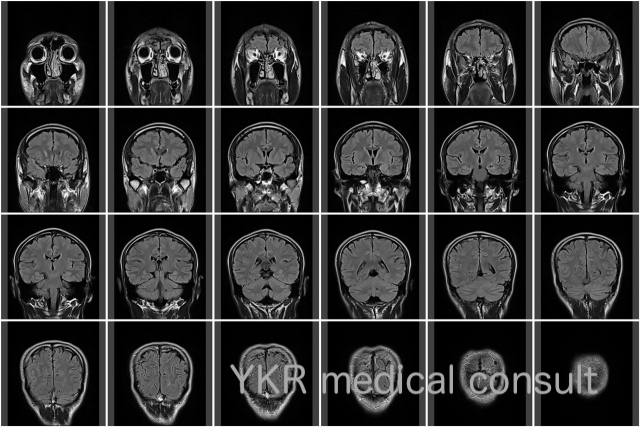

交通事故訴訟・反論意見書・脳神経領域(MTBI)1 依頼内容content(1) 事故および受傷の内容被害者は追突による交通事故で受傷した後に、頭痛・意欲低下を訴えて病院を受診した。その結果頭部MRIにて慢性硬膜下血腫が […]